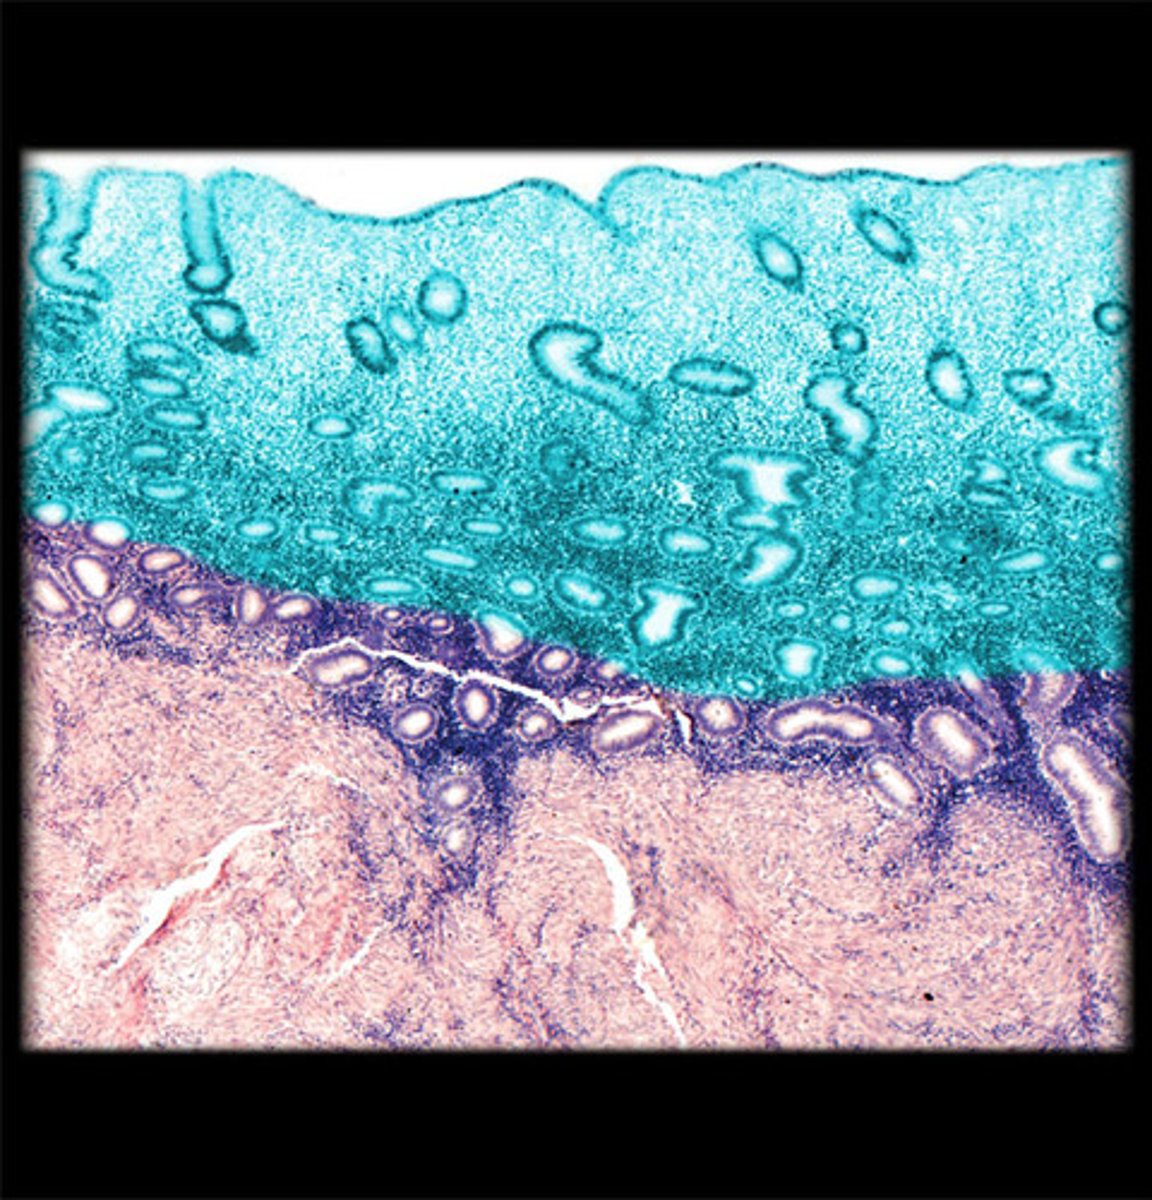

cortex

A

medulla

B

surface epithelium

tunica albuginea

endometrium

uterine glands

basal layer

in endometrium

functional layer

myometrium

smooth muscle

in myometrium it is made of

perimetrium

farthest layer

loose connective tissue, and simple squamous epithelium

what is perimetric made of